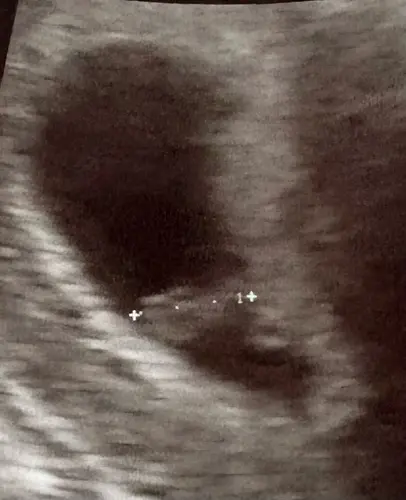

Zo leuk om dit allemaal te zien! Vorige week al een echo gehad toen dachten ze net 5 weken amper 4 mm wel kloppend hartje te zien. Vandaag extra ivm bloedverlies en al 1,4 cm🤩 en een snel en goed kloppend hartje. 7+4 volgens deze meting. Volgende week woensdag weer een echo 😊.